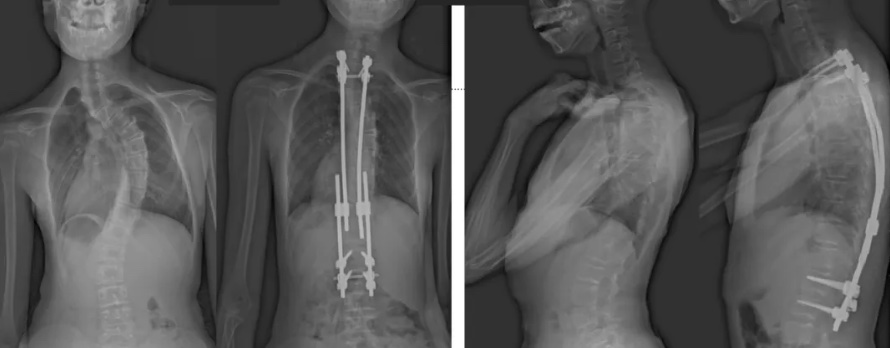

白瑪?shù)恼恍g(shù)前、術(shù)后對比圖(左側(cè));側(cè)位術(shù)前、術(shù)后對比圖(右側(cè))

術(shù)后第二天,白瑪就下地活動了。媽媽驚喜地發(fā)現(xiàn),白瑪一下子“長高”了近十厘米,重新抬起了頭,挺直了脊梁,肩膀也不歪了,可謂“脫胎換骨”。媽媽激動地錄制了一段白瑪走路的身影,把喜悅分享給全家。白瑪?shù)男g(shù)后檢查也提示,手術(shù)成功,恢復(fù)良好。